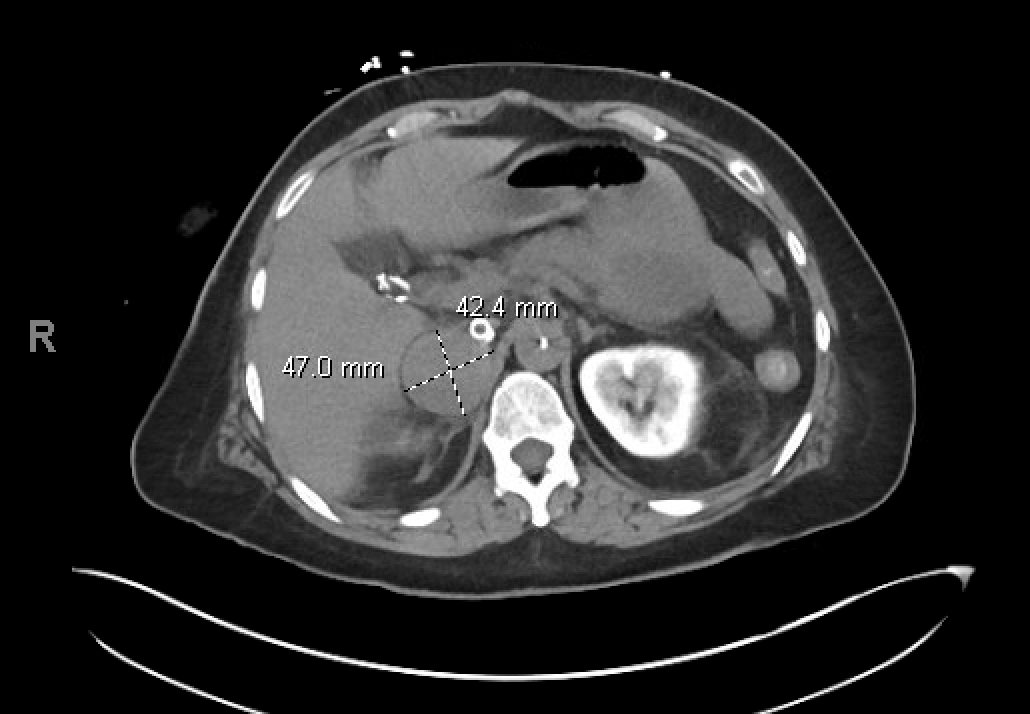

A 49-year-old female with past medical history of asthma initially presented to an outside hospital for palpitations, chest pain, and hypertension. Transthoracic echo (TTE) showed preserved left ventricle ejection fraction (LVEF) while cardiac MRI showed a LVEF of 43% with dilated left ventricle and diffuse global hypokinesis consistent with a dilated cardiomyopathy. She underwent a coronary angiogram demonstrating nonobstructive CAD. She was then discharged with readmission a month later at our hospital for chest tightness, palpitations, vomiting, weakness, and dizziness. Repeat TTE showed a drop in LVEF to 10-15%. She progressed to cardiogenic shock requiring BiPAP and inotrope initiation, with progressive shock and hypotension ultimately requiring Impella 5.5 and venoartrial ECMO. Abdominal imaging was notable for 4.7 x 4.2 cm right adrenal nodule and further workup with serum and urine metanephrines confirmed pheochromocytoma. While supported, the patient underwent right adrenalectomy with subsequent wean of mechanical circulatory support and biventricular recovery on TTE.